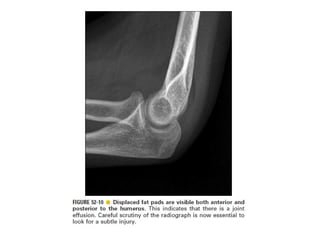

Skeletal trauma was presented by Dr Laith Fadhel with reference to Grainger's Diagnostic Radiology textbook. The presentation covered skeletal trauma as assessed through diagnostic radiology techniques. Key findings and treatments for skeletal injuries were likely discussed.